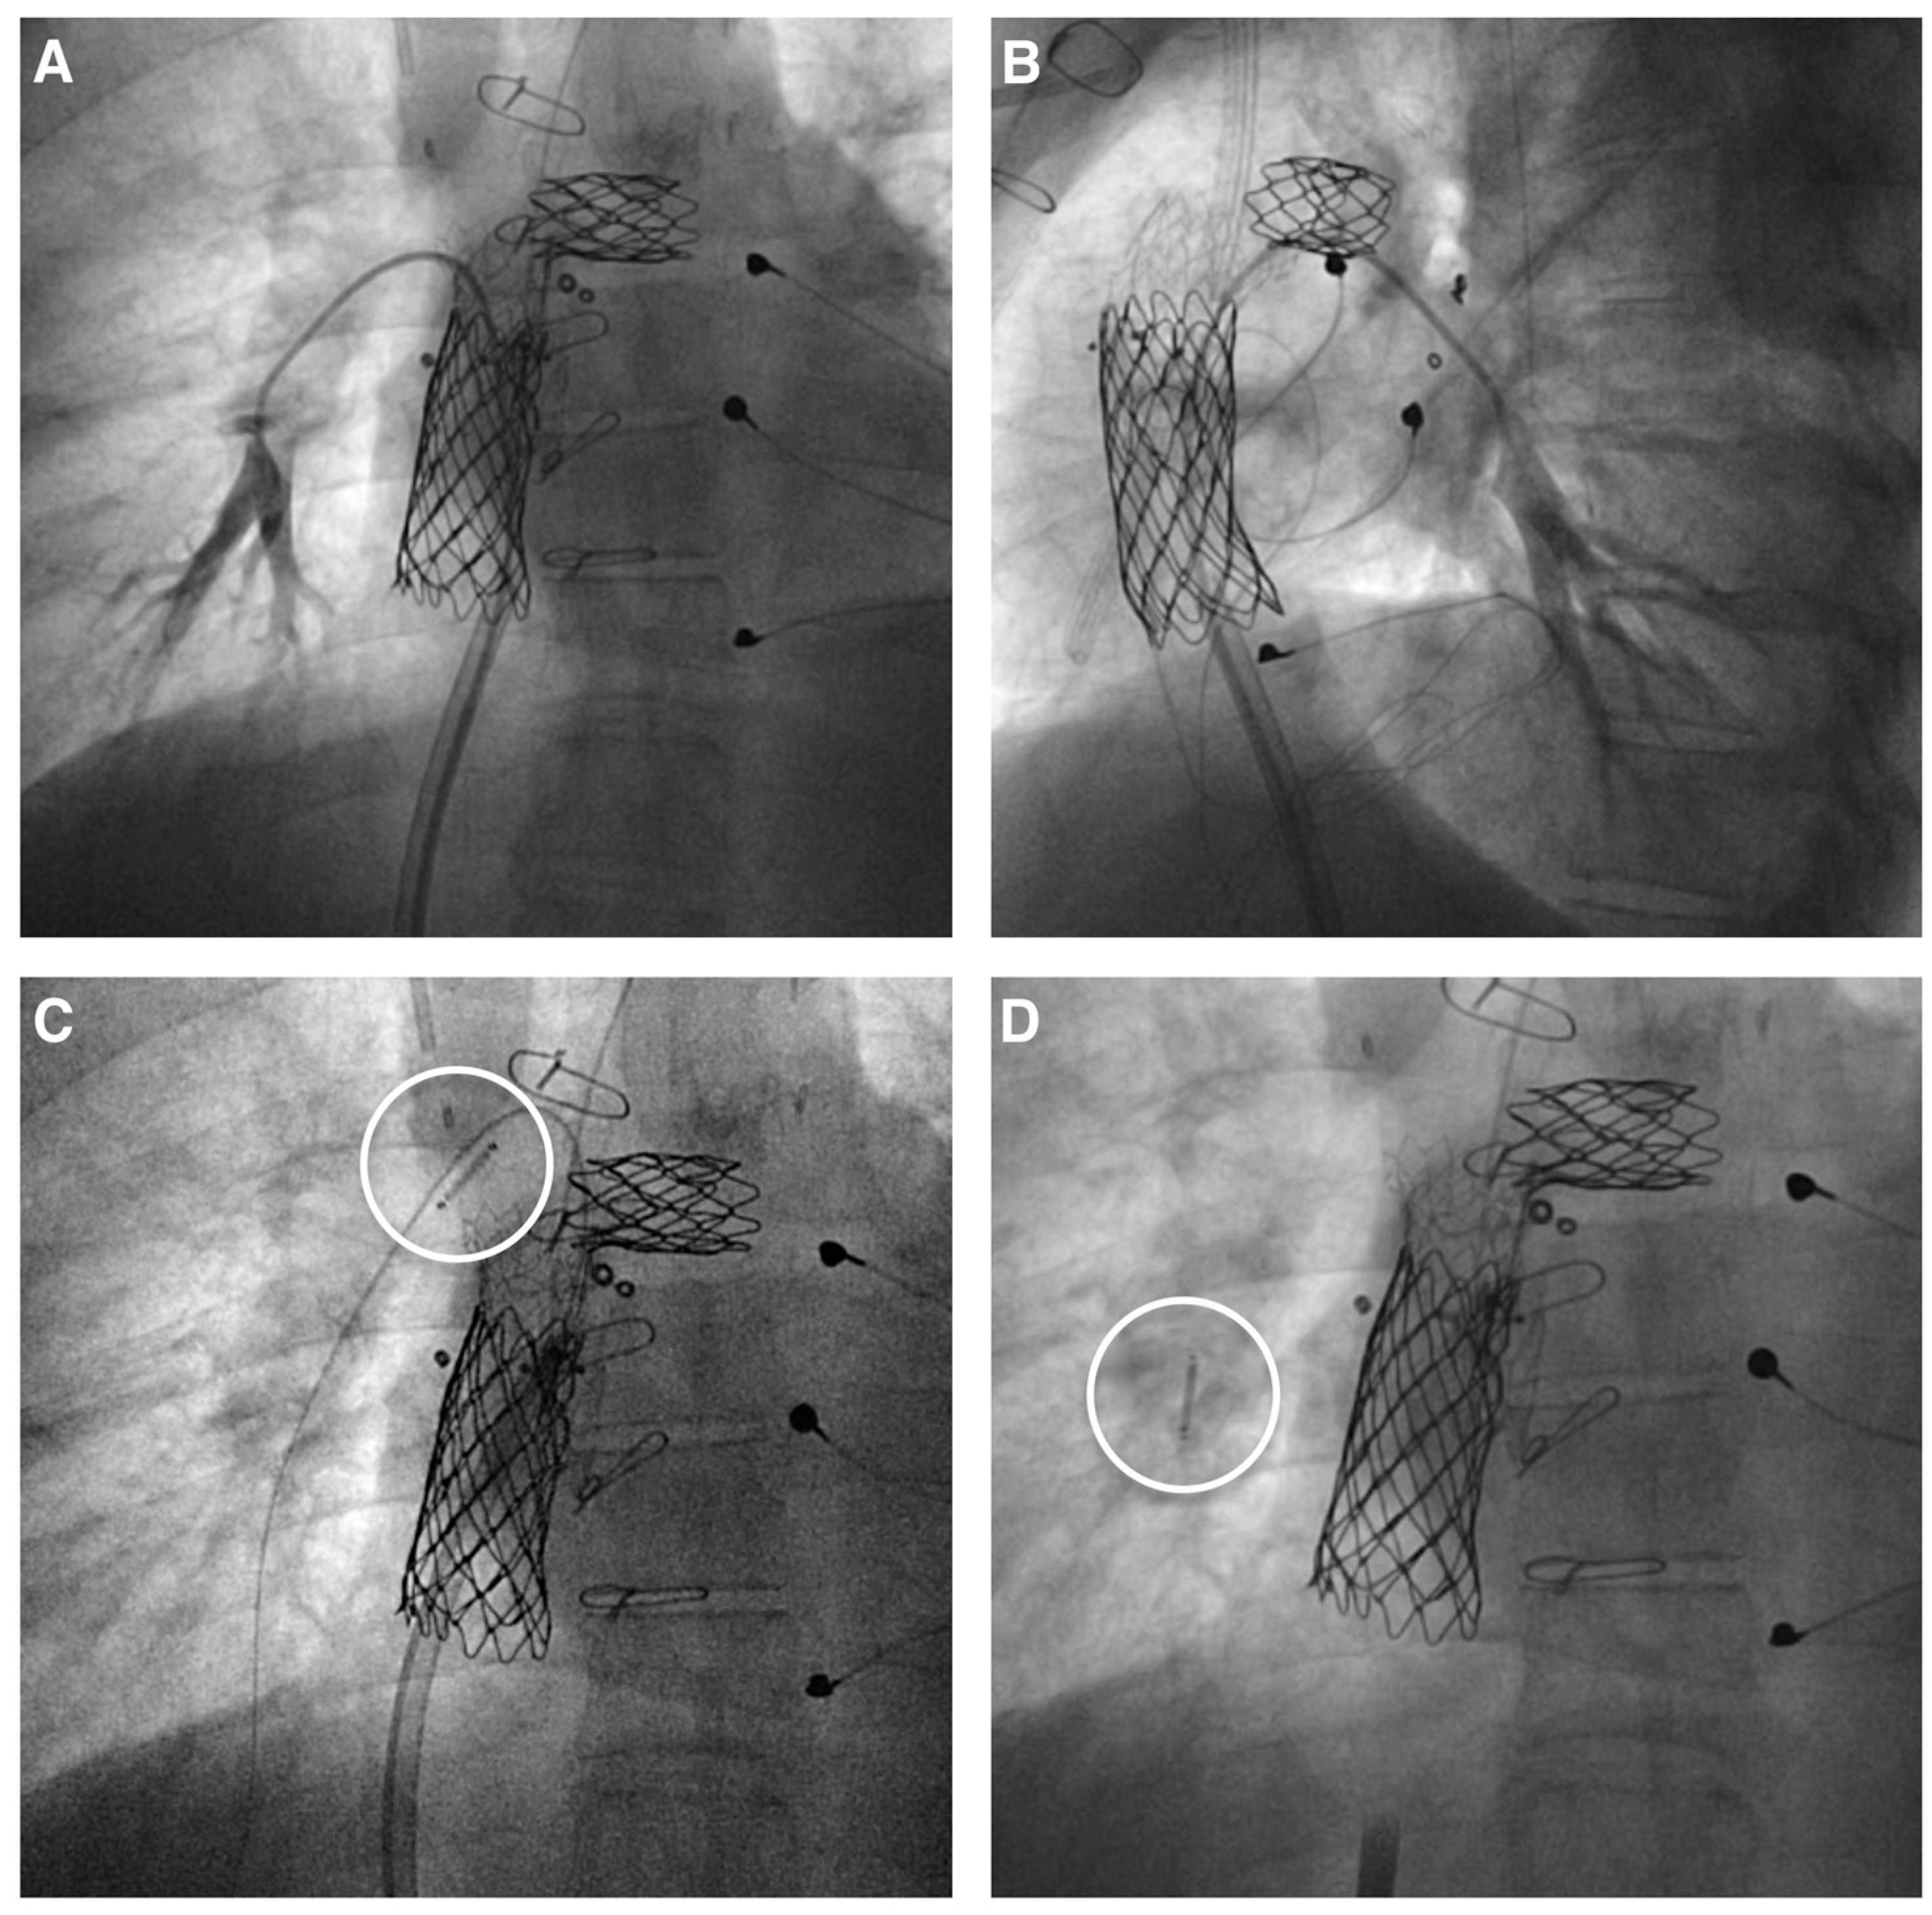

2. Procedure

- Salavitabar, A.; Bradley, E.A.; Chisolm, J.L.; Hickey, J.; Boe, B.A.; Armstrong, A.K.; Daniels, C.J.; Berman, D.P. Implantable pulmonary artery pres- 29. Sure monitoring device in patients with palliated congenital heart disease: Technical considerations and procedural outcomes. Catheter. Cardiovasc. Interv. 2020, 95, 270–279. [Google Scholar] [CrossRef] [PubMed]